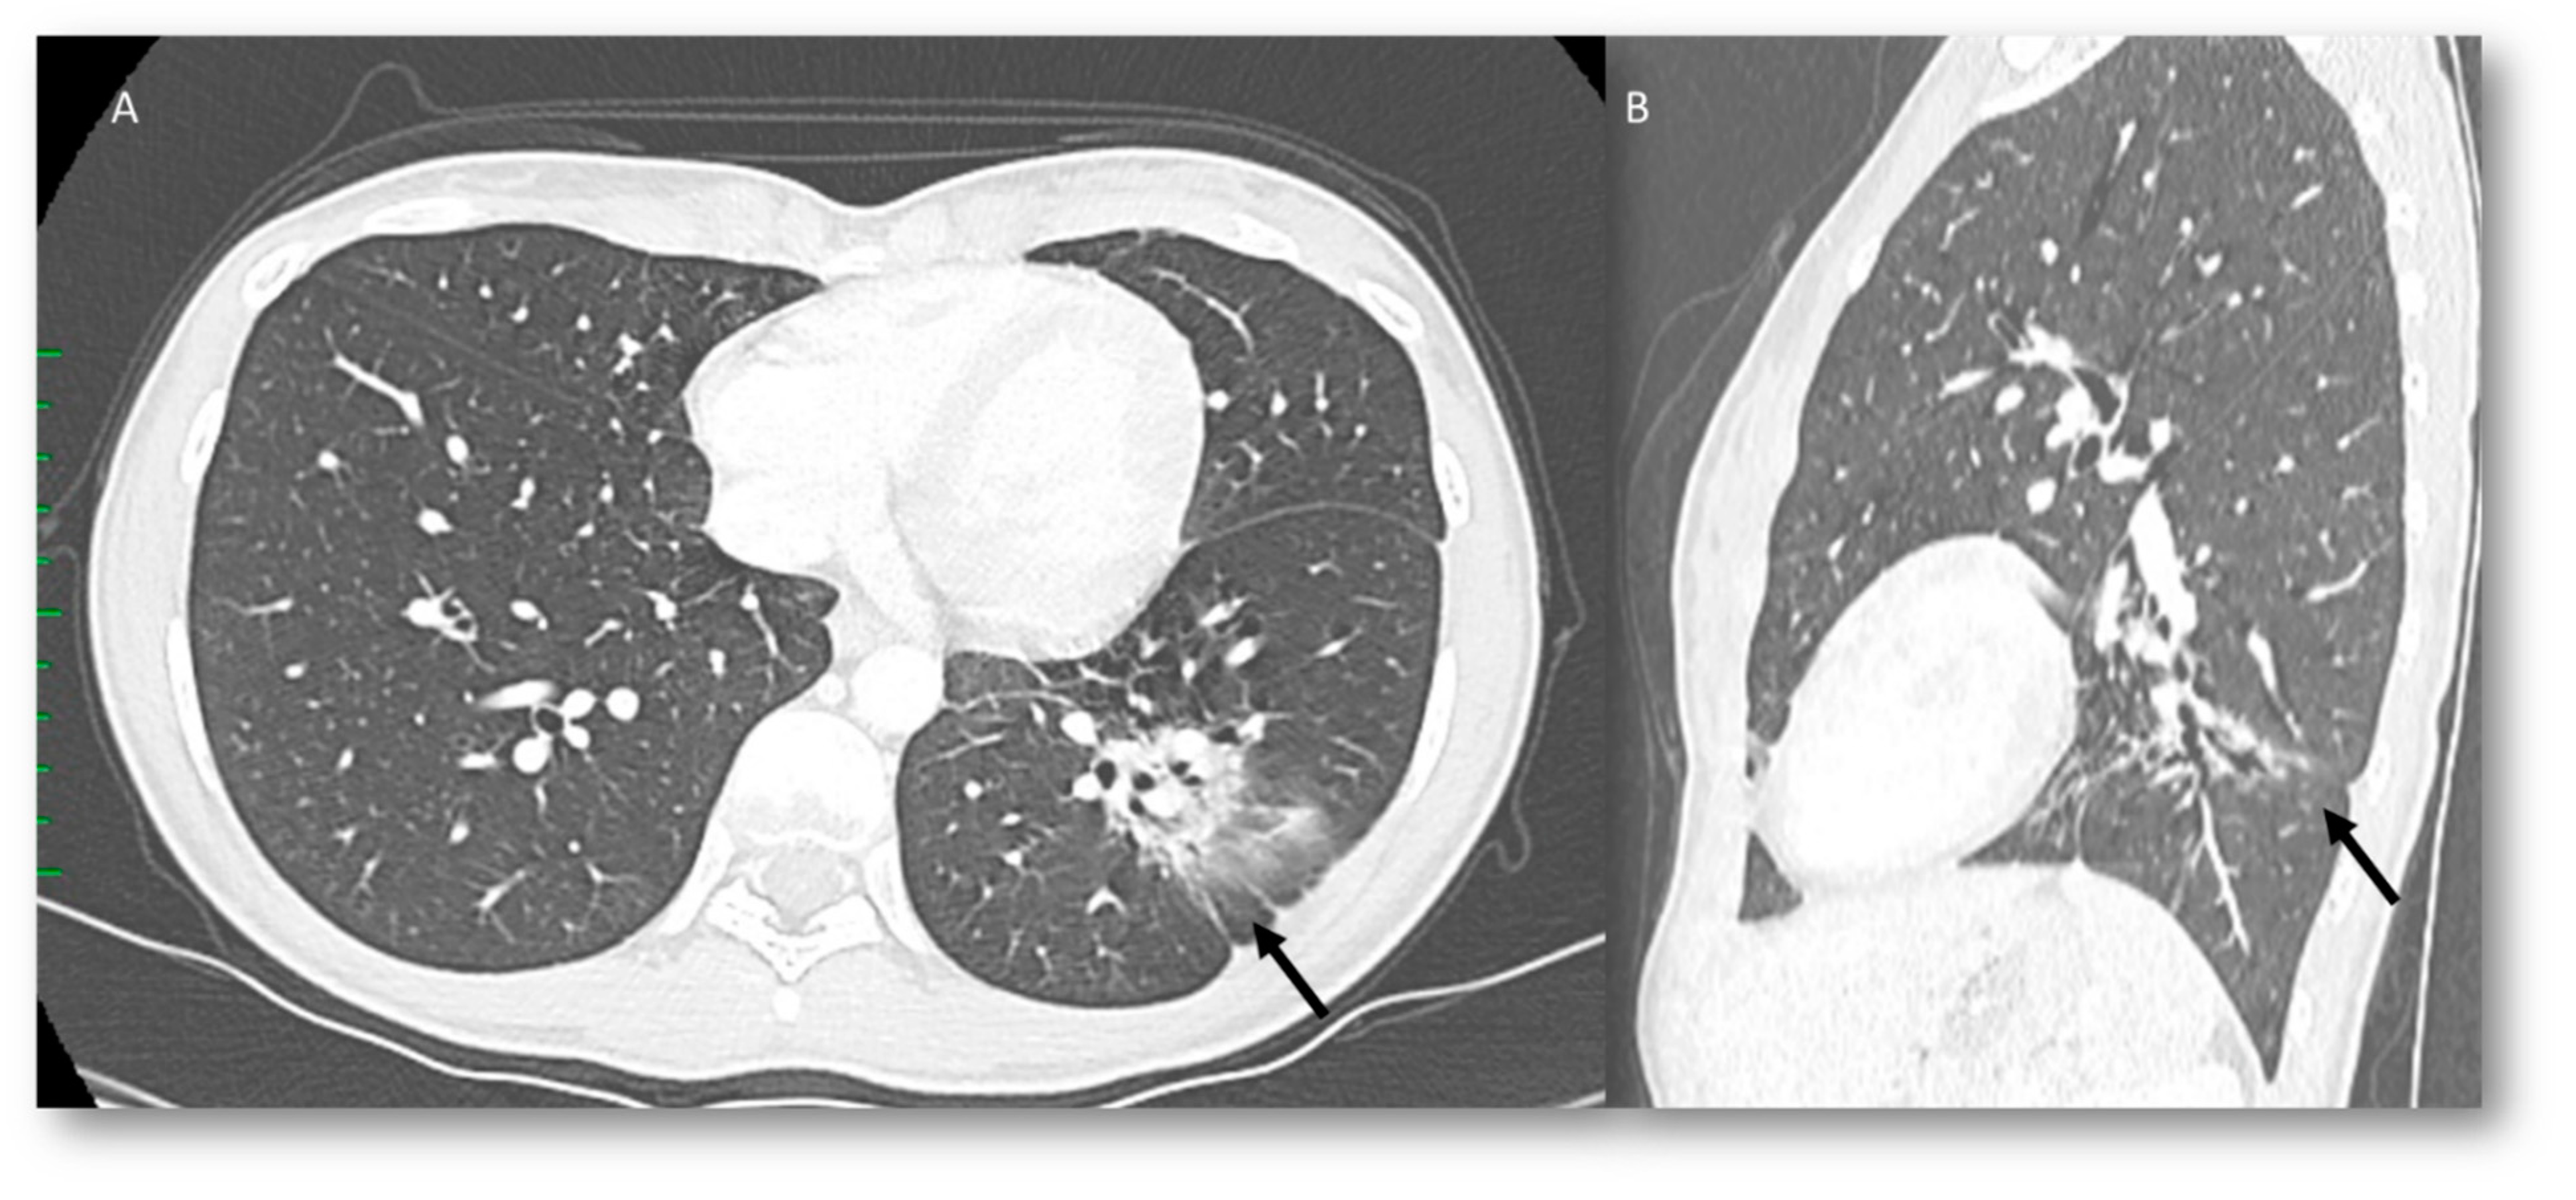

Radiation Recall Pneumonia

3.3. Radiation Pneumonia